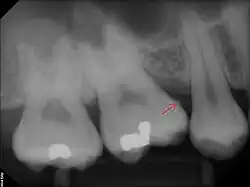

The following minerals are detectable in calculus by X-ray diffraction:

- brushite (CaHPO4 · 2 H2O)

- octacalcium phosphate (Ca8H2(PO4)6 · 5 H2O)

- magnesium-containing whitlockite (Ca9(Mg,Fe)(PO4)6(PO3OH))

- carbonate-containing hydroxyapatite (approximately Ca5(PO4)3OH but containing some carbonate).[16]